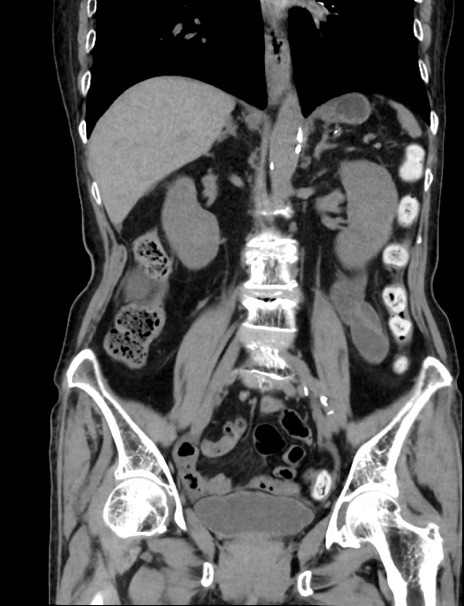

症例33(冠状断像)

【症例】70歳代 女性

【主訴】心窩部痛

【現病歴】延髄病変の精査・加療にて神経内科入院中。本日より心窩部痛あり。

【身体所見】右下腹部を中心に圧痛と反跳痛あり。

【データ】WBC 10900、CRP 0.02